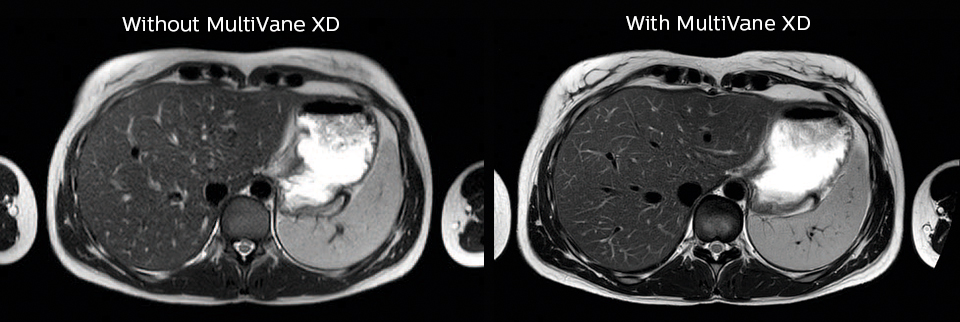

“We also love MultiVane XD for motion reduction in imaging.

We find this a huge step forward. We use it in the head, and of course in the upper abdomen, and the images are outstanding most of the time. And it can be combined with dS SENSE parallel imaging for speed.”

“We have compared image quality of FLAIR with MultiVane XD versus FLAIR without MultiVane XD. In 15 of the 40 patients studied, we saw motion artifacts on plain FLAIR brain images. The FLAIR images with MultiVane XD were motion-free in 39 of 40 patients and showed slight motion artifacts in only one patient.”